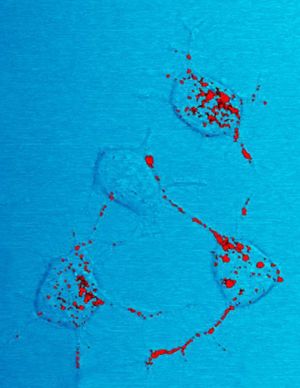

프리온은 중추 신경계에 세포 외적으로 응집하여 아밀로이드로 알려진 플라크를 형성하고, 정상적인 조직 구조를 파괴하여 신경퇴행성 질환을 일으킨다.[220] 이러한 현상은 뉴런의 공포 형성으로 인해 조직 내에 "구멍"이 보이는 스펀지 모양의 구조로 나타나며, 성상교세포증 및 염증 반응의 부재와 같은 조직학적 변화가 동반된다.[75][76]

thumb